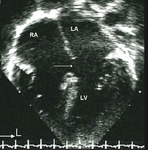

Imagem de ecocardiografia apical de 4 câmaras revelando dilatação do ventrículo direito em um paciente com defeito do septo atrial (DSA). (AD) átrio direito; (VD) ventrículo direito; (VE) ventrículo esquerdo

Imagem cedida por Patrick W. O'Leary, MD